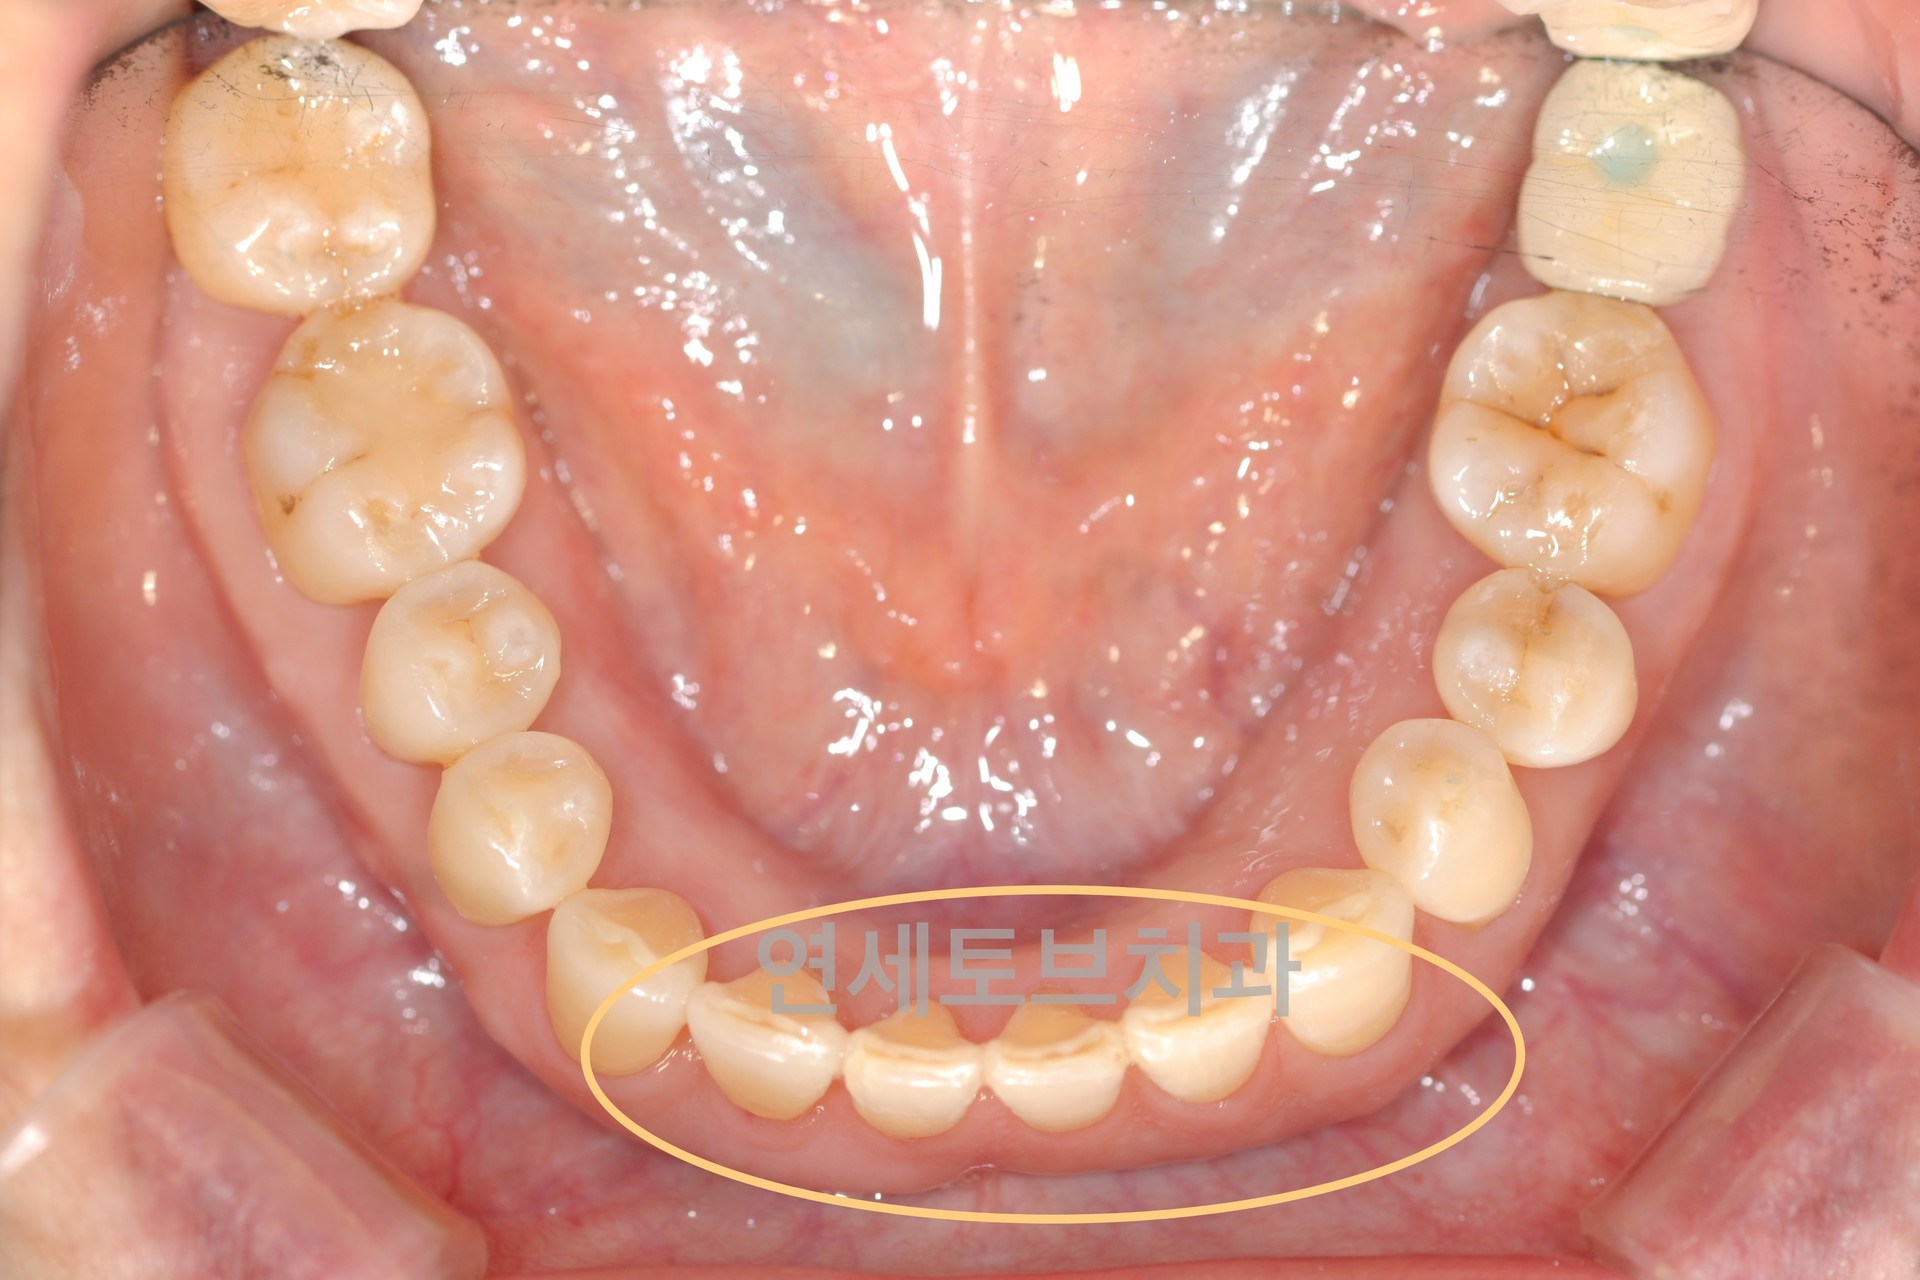

After

중장년층(40대 이상)에서 앞니 부분 교정은 주로 나이가 들면서 앞니 배열이 흐트러지거나 치아 사이에 공간이 생기는 문제를 해결하는 치료입니다. 젊었을 때는 가지런했던 앞니가 나이가 들수록 점점 삐뚤어지거나, 잇몸 질환 등으로 인해 치아가 이동하는 현상이 흔하게 나타납니다